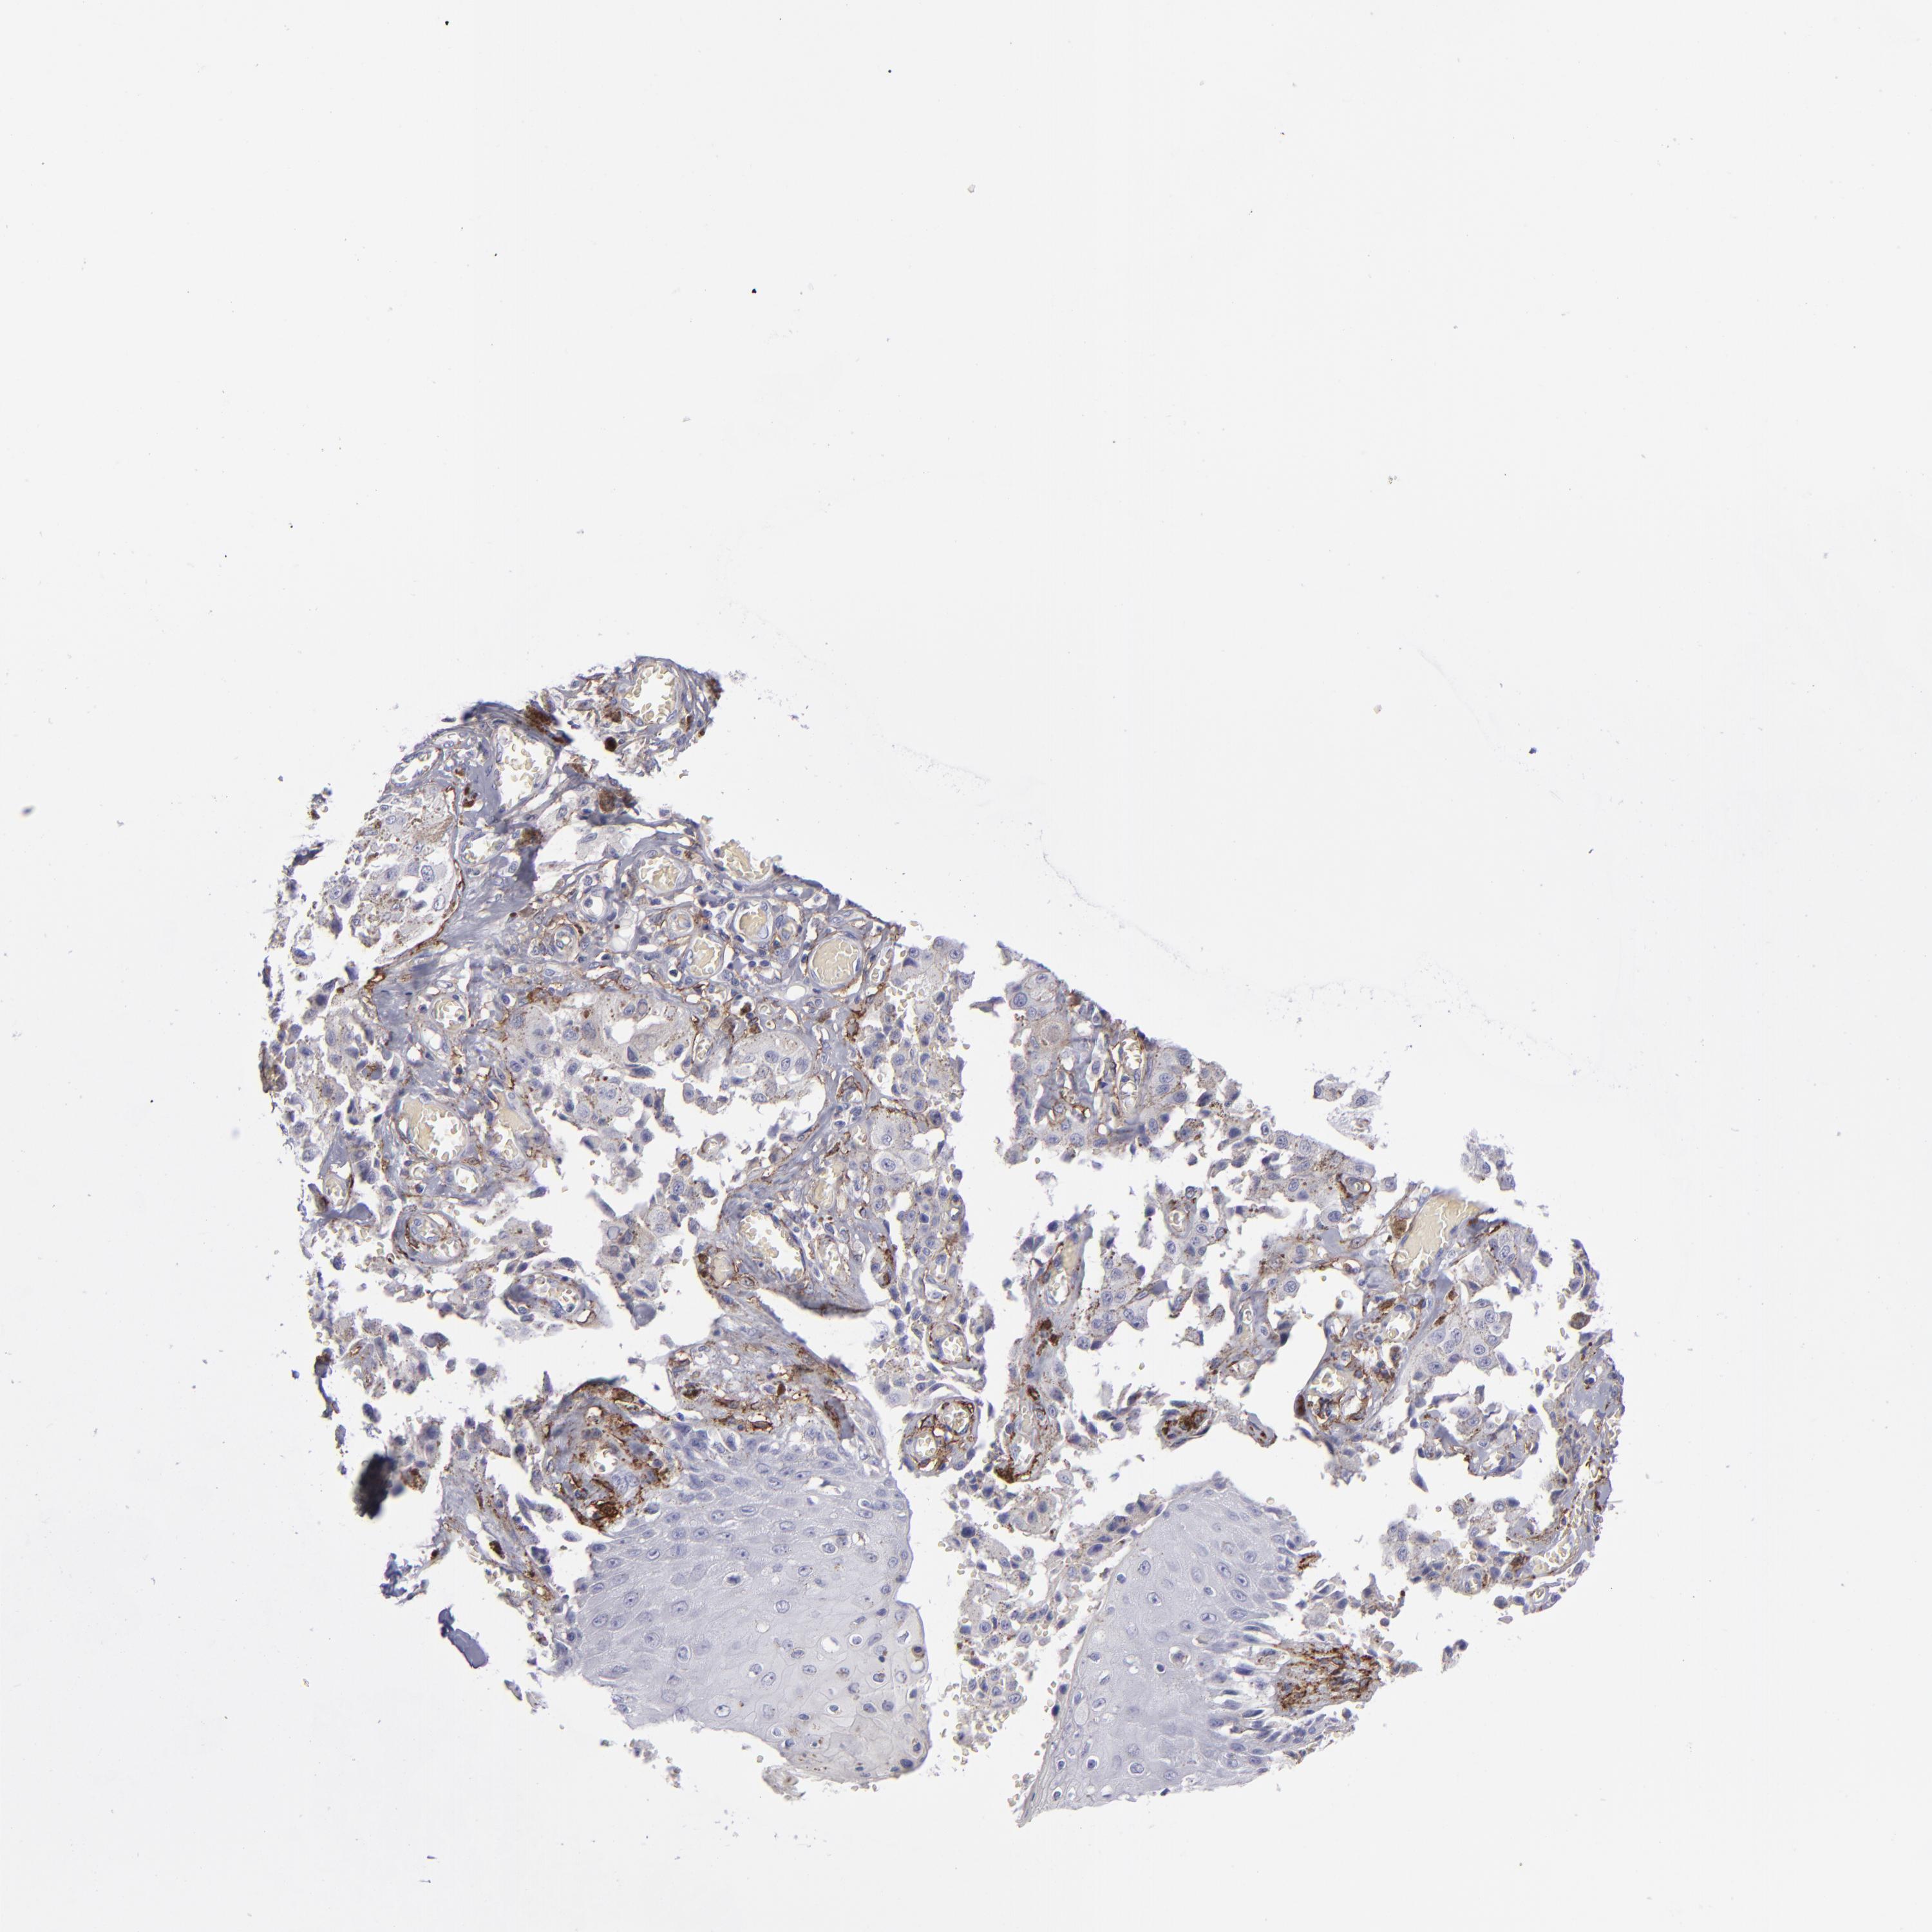

MELANOMA - Protein expressioni

A mouse-over function shows sample information and annotation data. Click on an image to view it in a full screen mode. Samples can be filtered based on level of antibody staining by selecting one or several of the following categories: high, medium, low and not detected. The assay and annotation is described here.

Note that samples used for immunohistochemistry by the Human Protein Atlas do not correspond to samples in the TCGA dataset.

Antibody stainingi

Antibody staining in the annotated cell types in the current human tissue is reported as not detected, low, medium, or high, based on conventional immunohistochemistry profiling in selected tissues. This score is based on the combination of the staining intensity and fraction of stained cells.

Each image is clickable and will lead to virtual microscopy that enables deeper exploration of all samples and also displays staining intensity scores, fraction scores and subcellular localization as well as patient and tissue information for each sample.

Antibody HPA004625

Antibody CAB002417

Staining

High

Medium

Low

Not detected

Intensity

Strong

Moderate

Weak

Negative

Quantity

>75%

75%-25%

<25%

None

Location

Nuclear

Cytoplasmic/membranous

Cytoplasmic/membranous,nuclear

Malignant melanoma, NOS

Malignant melanoma, Metastatic site